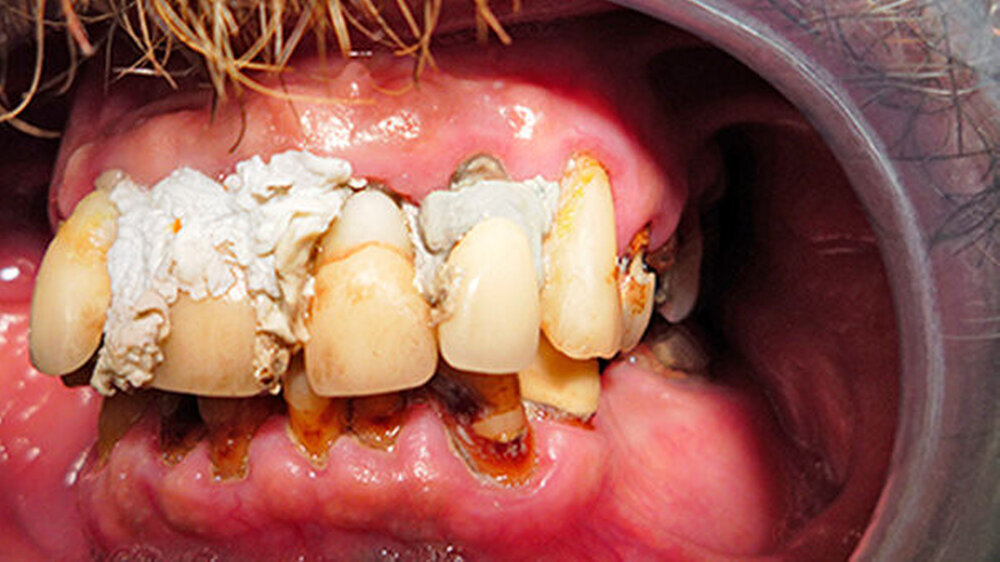

5. Dezember 2009: Alle Frontzähne zeigten Lockerungsgrad III - abbeißen konnte der Patient deshalb schon seit längerer Zeit nicht mehr richtig. Zahnschmerzen verspürte er jedoch noch nicht, weshalb er auch keine Veranlassung sah, zum Zahnarzt zu gehen.

Seine Idee stattdessen: die Zähne selbst zu befestigen. Da er als Handwerker ist er im Umgang mit Baumaterialien versiert ist, sah er sich dieser Herausforderung gewachsen. Er kaufte sich im Baumarkt Fugendichtsilikon und umspritzte damit seine Zähne zur Befestigung. Farblich wählte er "manhattan-grau" und "steingrau" - diese Töne waren billiger als weißes Silikon.